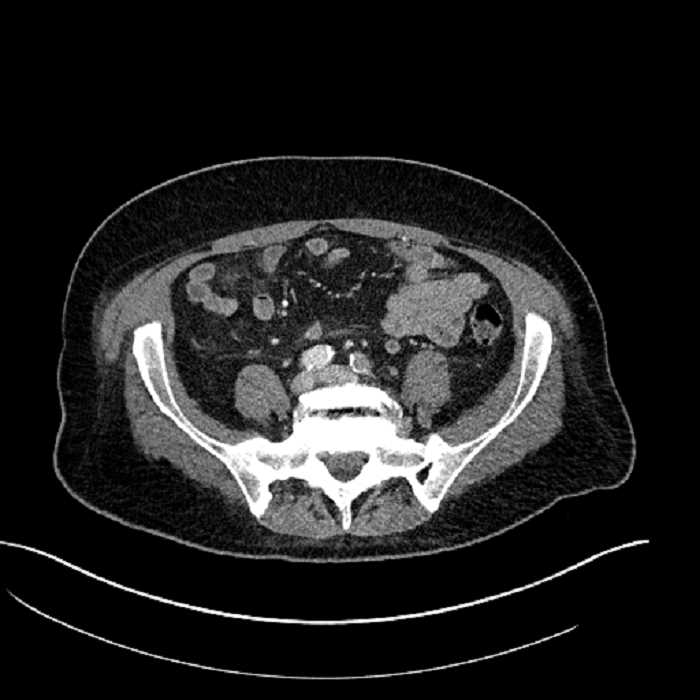

• Mild mural thickening of a segment of the sigmoid colon with adjacent fat stranding and a 1.5 cm fluid and gas collection along the tip of an inflamed diverticulum

• Loss of the normal fat plane between this collection and adjacent loops of small bowel, which demonstrate mural thickening

• No bowel obstruction

Acute sigmoid diverticulitis complicated by a small contained perforation and a large abscess in the right hepatic lobe. Additional small subcapsular abscesses along the anterior margin of the left hepatic lobe.

Additionally, loss of the normal fat plane between the peridiverticular collection and adjacent thickened loops of small bowel raises the potential for an enterocolonic fistula.

Hepatic abscess showing the double target sign with low density internally surrounded by a thin inner enhancing rim (red arrow) and ill-defined outer low density rim (yellow arrow). Blue arrow indicates an internal septation. Red arrows: additional smaller subcapsular abscesses. Red arrow: focal contained perforation associated with diverticulitis.